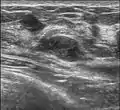

Fibroadenoma in ultrasound Fibroadenoma in ultrasound